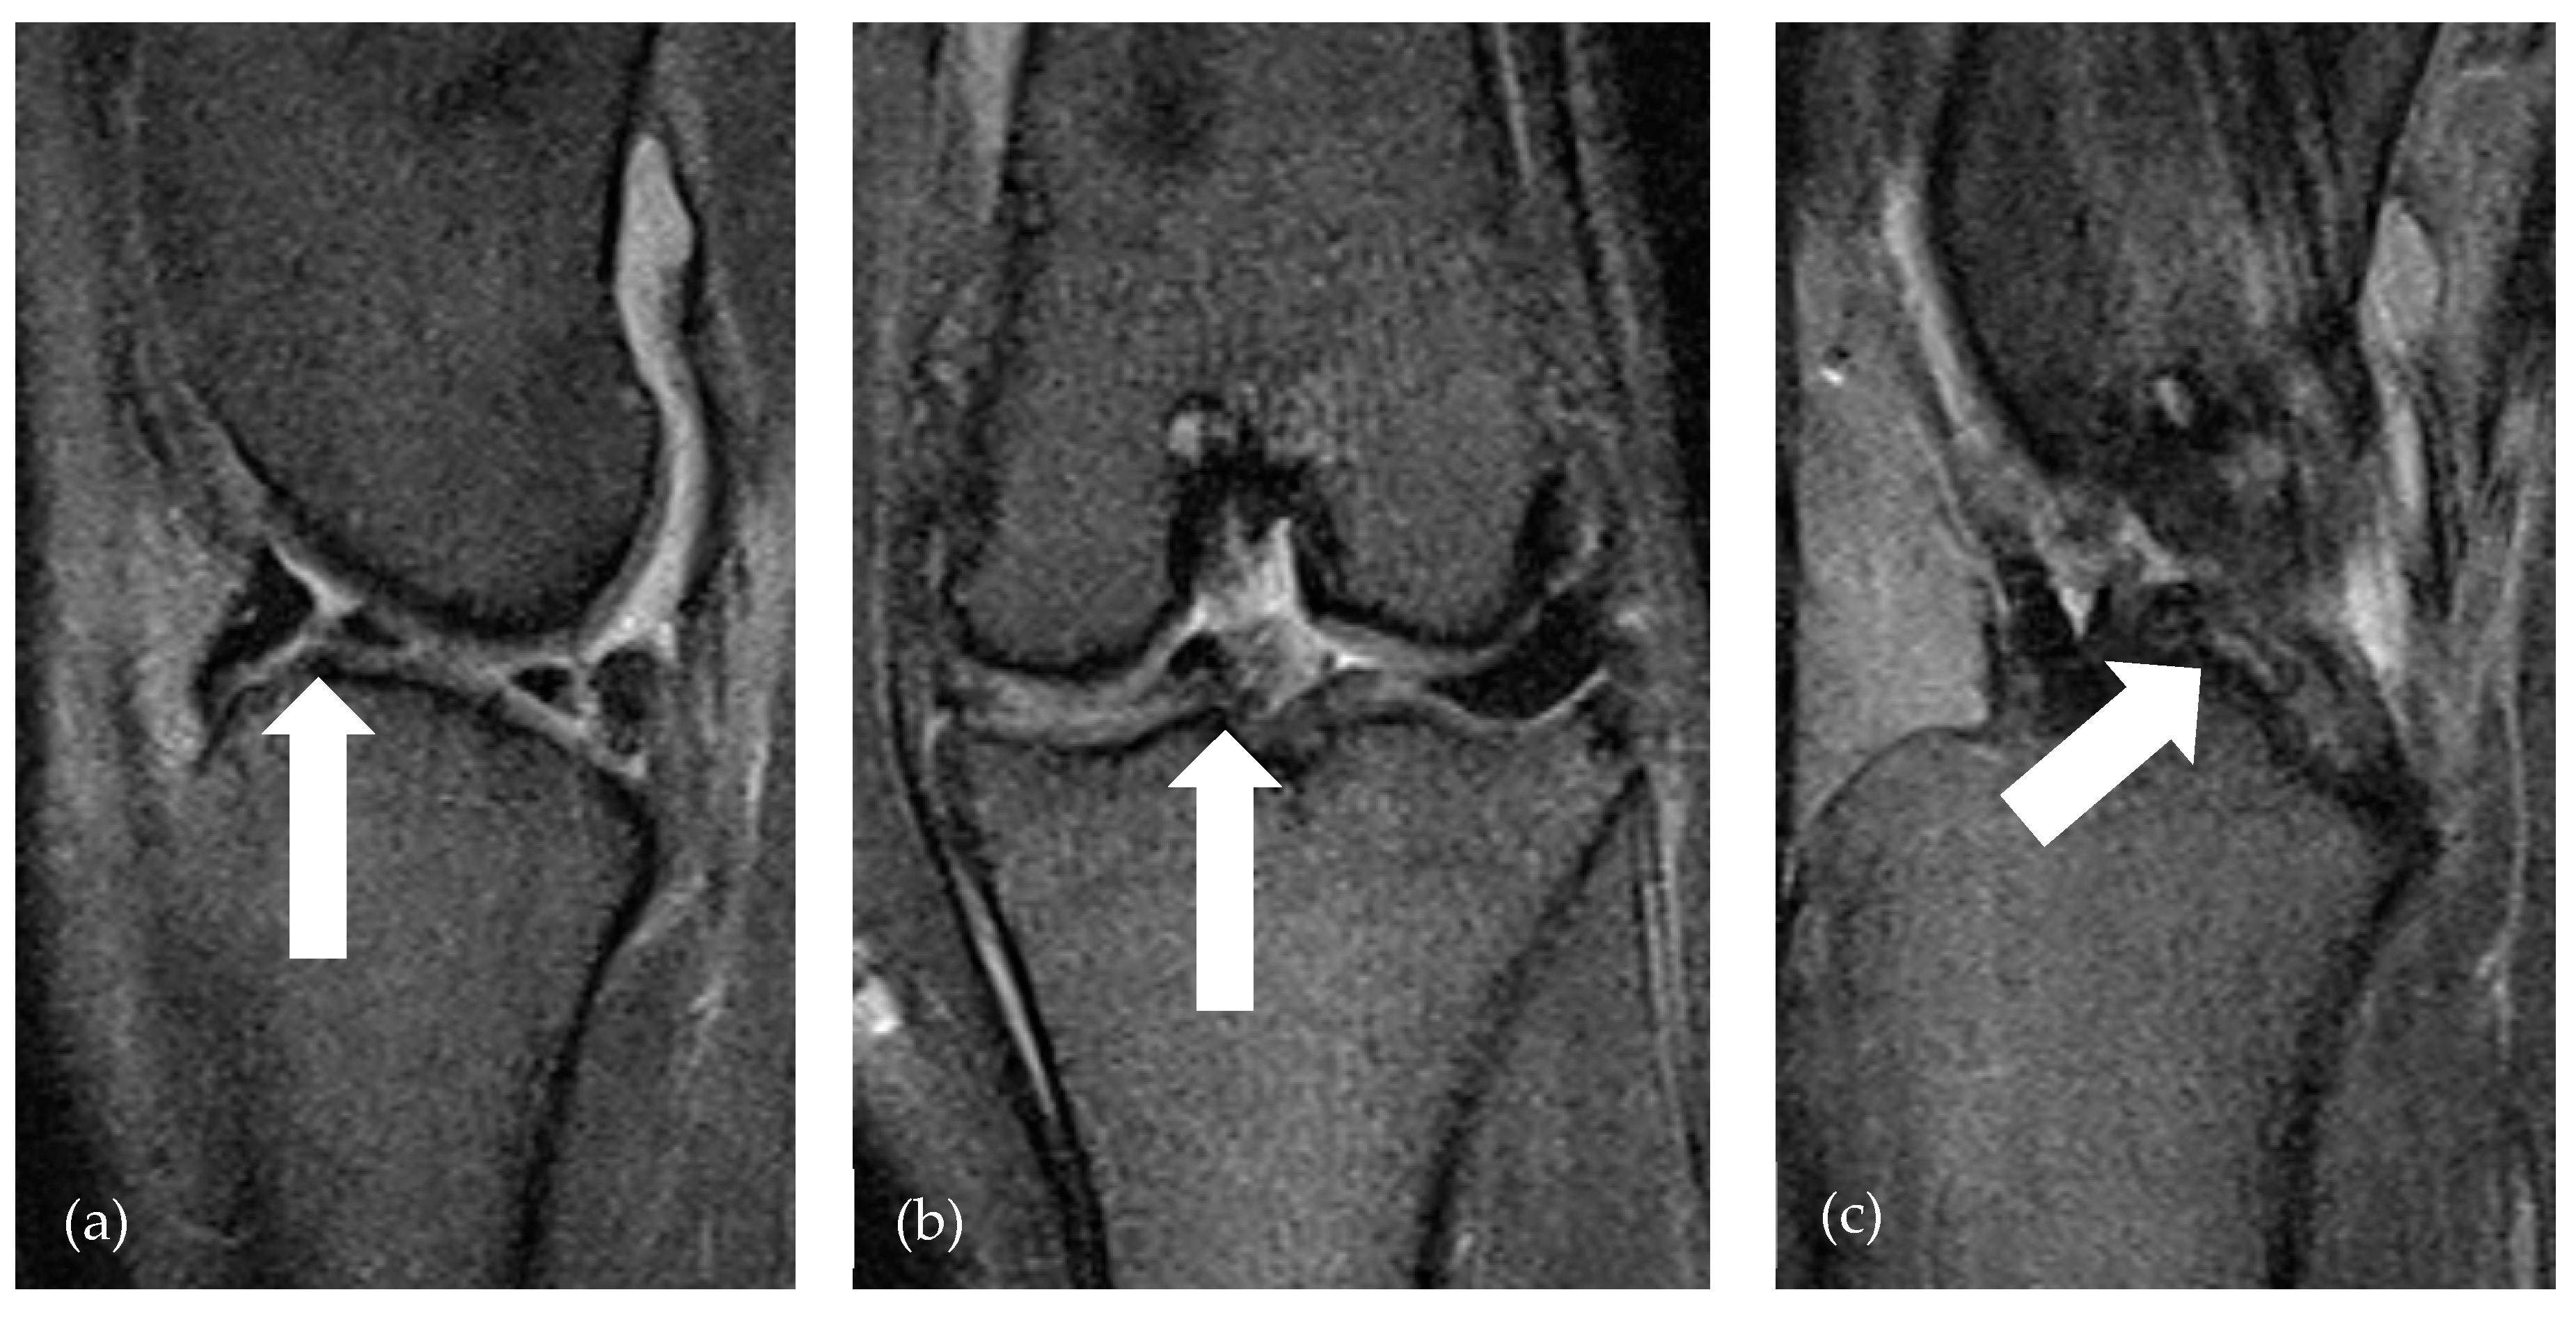

| Grade | Meniscal Pathology |

|---|---|

| 0 | without pathological findings |

| 1 | diffusely increased signal—degeneration |

| 2 | mild axial fibrillation; mildly irregular axial border |

| 3 | severe axial fibrillation; blunt axial border without presence of fragments |

| 4 | nondisplaced rupture (linear signal increase with contact to one or two surfaces) |

| 5 | rupture with displaced fragment, bucket handle tear |

| 6 | folded meniscus |

| 7 | large parts of meniscus missing, multiple fragments |